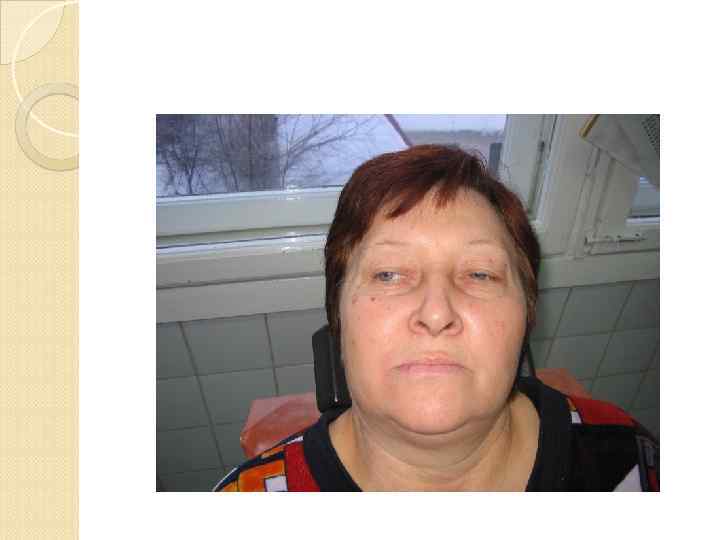

Местные признаки болезни Инфильтрация тканей в поднижнечелюстно й области. Воспалительная контрактура I степени.

Местные признаки болезни Инфильтрация тканей в поднижнечелюстно й области. Воспалительная контрактура I степени.